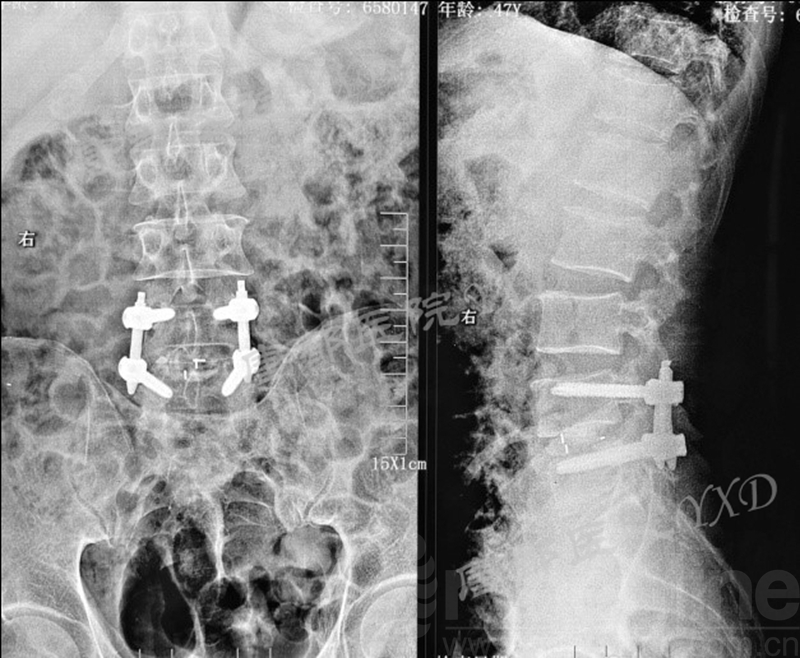

影像学检查:

诊断:腰椎椎间融合术后融合器后移

手术方案:显微镜辅助MI-TLIF腰椎翻修术

术后疗效:VAS左下肢1分、腰1分;左侧直腿抬高试验、加强试验阴性。